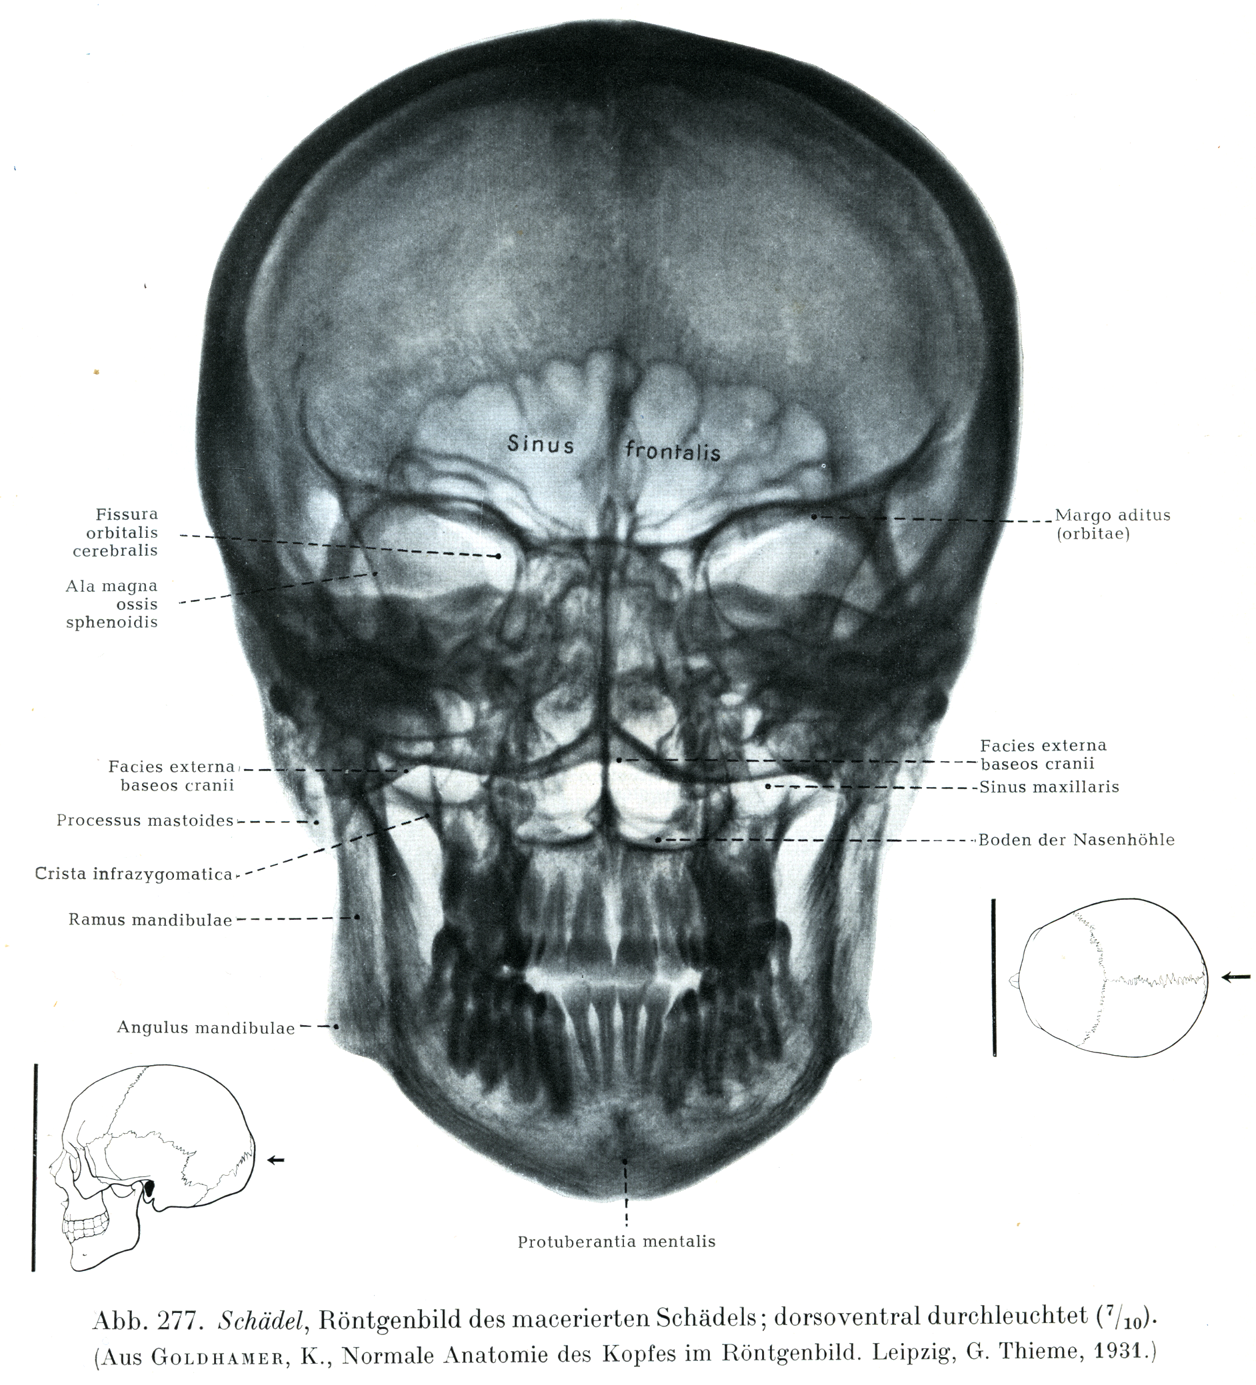

Rauber Kopsch Band1. Abb-277

[図277]

さらした頭蓋のレントゲン像

背腹照射(7/10)